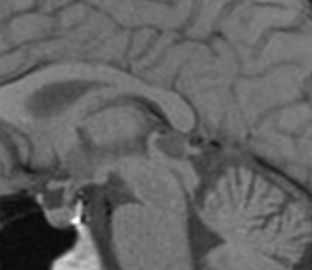

Пинеальная киста расположена в проекции шишковидной железы. Встречается с частотой 4-11%. Размеры обычно не превышают 1 см, но изредка встречаются больших размеров. В таких случаях она вызывает окклюзионную гидроцефалию. При МРТ головного мозга она имеет все признаки кисты с примесью белка в жидкости, то есть немного светлая на Т1-зависимых МРТ. Изредка встречается геморрагическое содержимое. Киста может по усиливаться периферии при МРТ головного мозга с контрастированием.

МРТ головного мозга. Т1-взвешенная сагиттальная МРТ. Пинеальная киста.